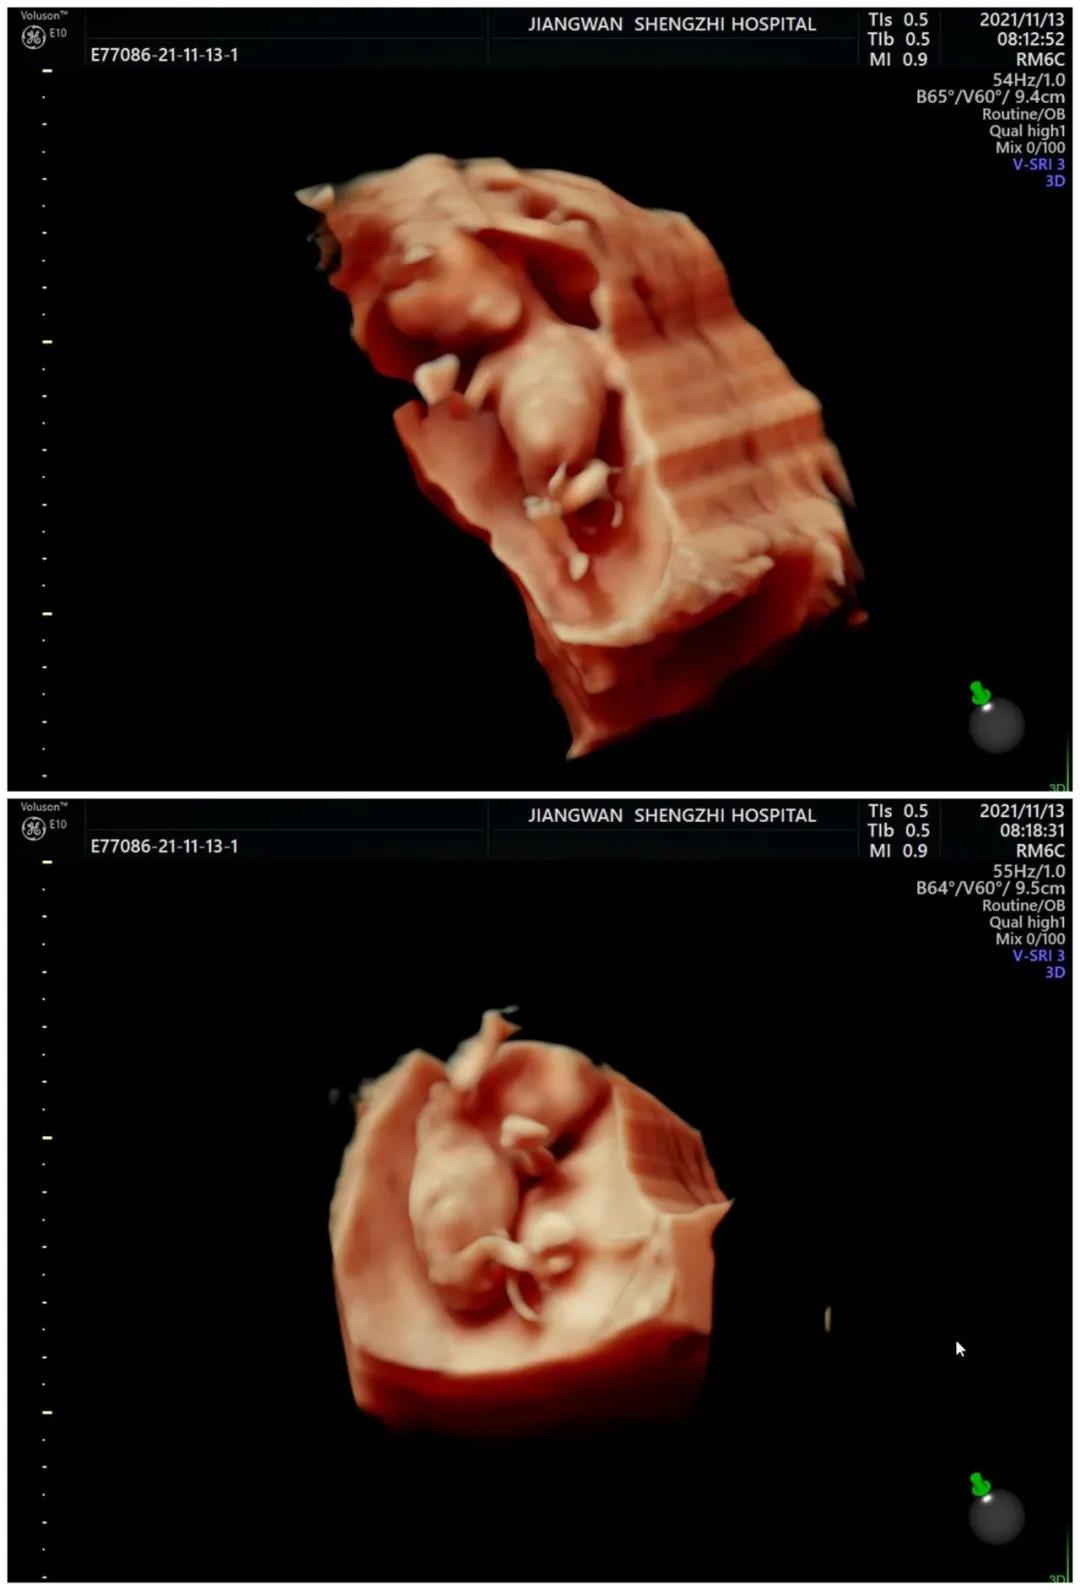

张文燕医生说的小目标便是首先在B超上看到孕囊,接着是宝贝的胎心、胎芽,再是胎盘、脐带,当第四次顺利进行NT检查时,不仅小吴流下了幸福的眼泪,一直在身后默默帮助和支持她的医护人员也终于放下心来,由衷地为她感到高兴。

清晰精准的四维彩超影像